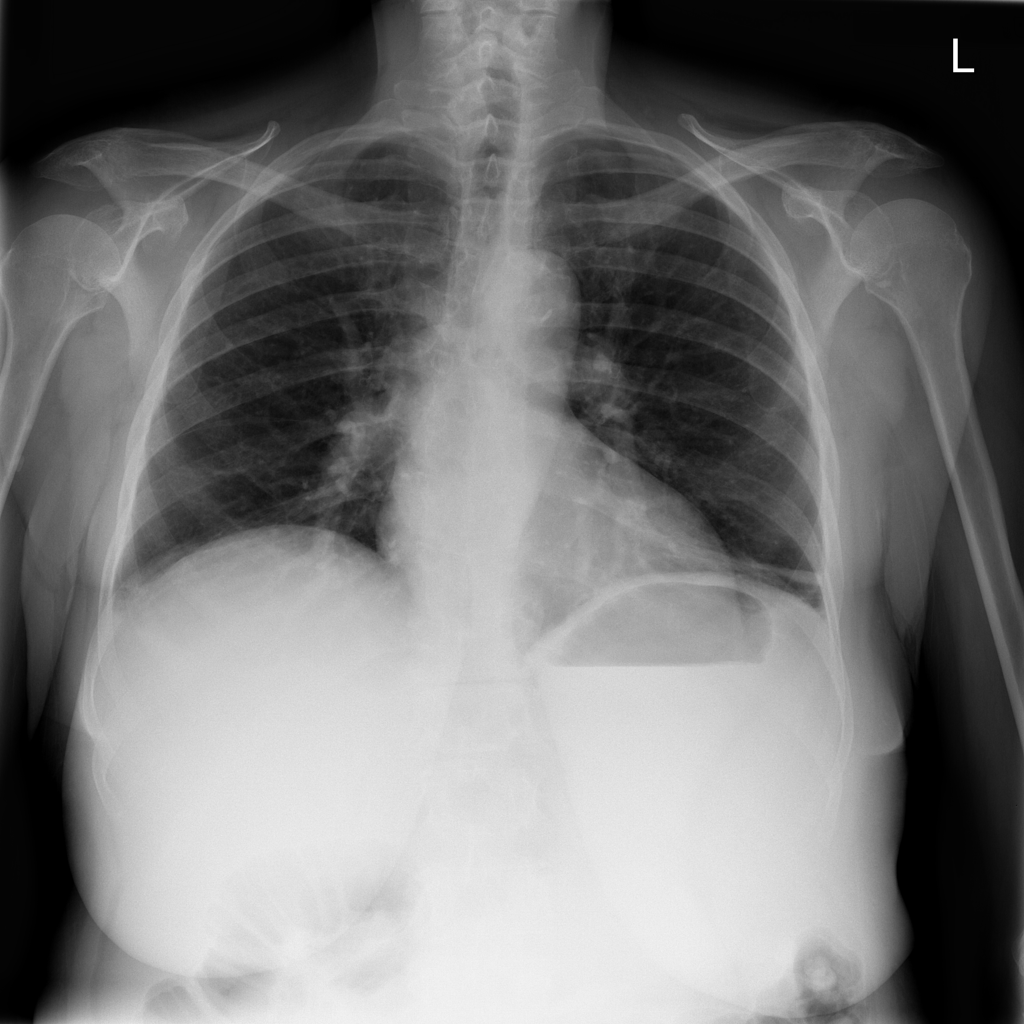

PAT-DB80 · IMG-000Atelectasis

PAT-DB80 · IMG-000

PA